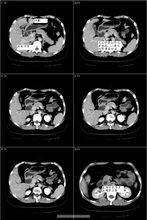

影像診斷

腹部X線平片、膽囊和膽道X線造影、腹部B超和腹部CT檢查、內鏡逆行胰膽管造影(ERCP)和經皮肝穿刺膽道造影(PTC),均有助於阻塞性黃疸的定性和定位診斷。